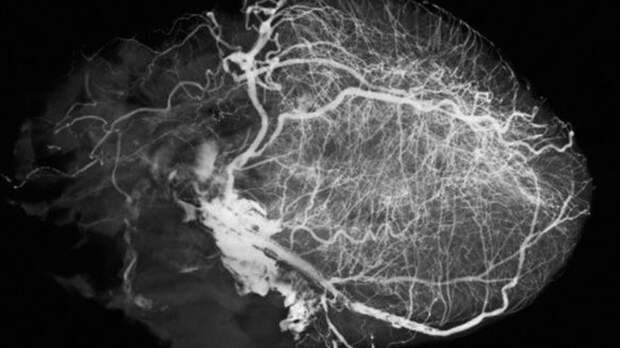

МР-ангиография - вид рентгенологического обследования, использующий контрастирующее вещество для детального изучения сосудистой системы. Этот метод эффективен для раннего выявления серьезных заболеваний, включая проблемы с артериями, венами, капиллярами, а также сосудистой системой лимфы.

Для диагностики используется оборудование, включая магнитно-резонансные томографы и флюорографические приборы с возможностью скоростной видеосъемки. Это позволяет получать высококачественные изображения сердечно-сосудистой системы, которые важны для диагностики лечения.

Сканирование может требовать локальной анестезии. Рентгенолог проводит дезинфекцию кожи, делает маленький разрез для доступа к артерии, через который вводится катетер с контрастным веществом. В процессе обследования создаются детализированные изображения, позволяющие оценить состояние сосудов.

Контраст распределяется по сосудистой системе, позволяя детально исследовать структуру и функцию сосудов. После обследования контраст выводится почками, а место введения катетера закрывается стерильной повязкой.